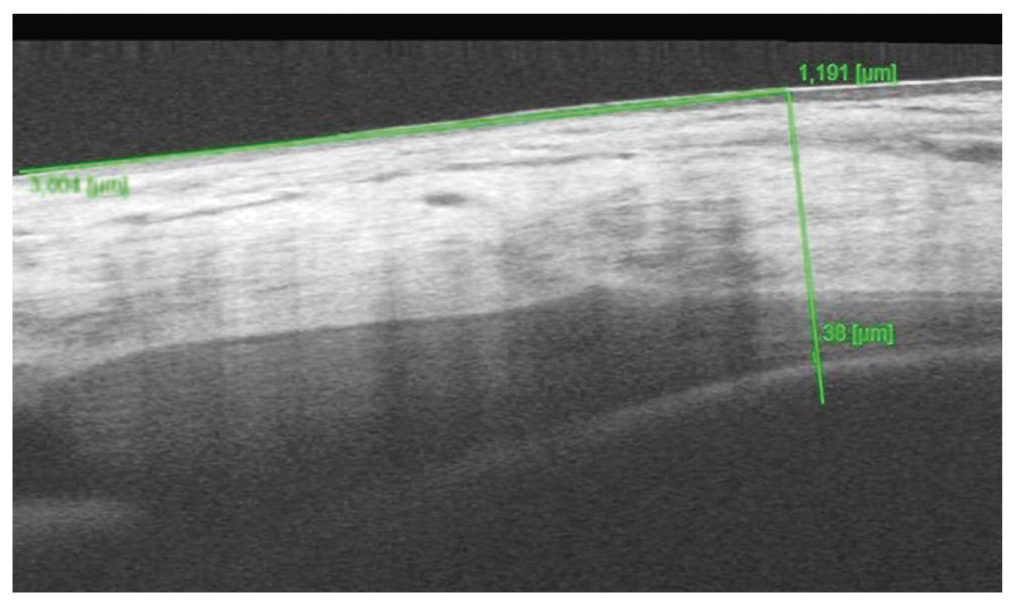

ОКТ переднего отрезка глаза по предлагаемому способу. OD: толщина сосудистого слоя цилиарного тела во внутреннем отделе 44 мкм (рис. 7), в наружном отделе — 36 мкм; OS — 37 мкм и 29 мкм соответственно; ОКТ заднего отрезка глаза без особенностей.

Рис. 7. Толщина сосудистого слоя цилиарного тела во внутреннем отделе правого глаза на 35-й неделе беременности

Fig. 7. Thickness of the vascular layer of the ciliary body in the inner part of the right eye at 35 weeks of gestation

При проведении А-ОКТ обоих глаз в сравнении с исследованием, проведённым на 19-й неделе, увеличилось количество микро- и макроаневризм, выявлена также папиллярная и ретинальная неоваскуляризация.

Установлен диагноз: «Пролиферативная диабетическая ретинопатия правого глаза. Препролиферативная диабетическая ретинопатия левого глаза».